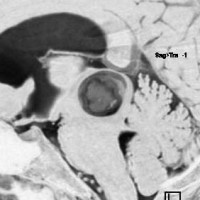

2008年の中脳毛様細胞性星細胞腫の手術ビデオ

左は術前,右は手術直後のMRIです。このビデオを見て,およその手技の順番のみ把握して下さい。